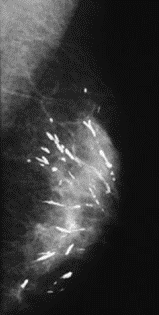

Na którym obrazie rentgenowskim sutka uwidoczniono zmianę patologiczną w obrębie węzłów chłonnych?

A. Obraz 2

B. Obraz 3

C. Obraz 4

D. Obraz 1